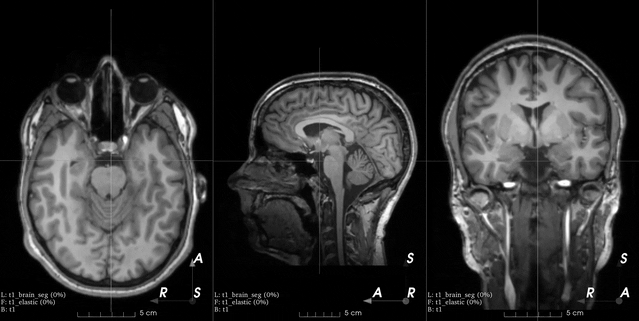

Note that control points outside the image bounds are not showed in the

example image (they would also be red as we set locked_borders

to 2).